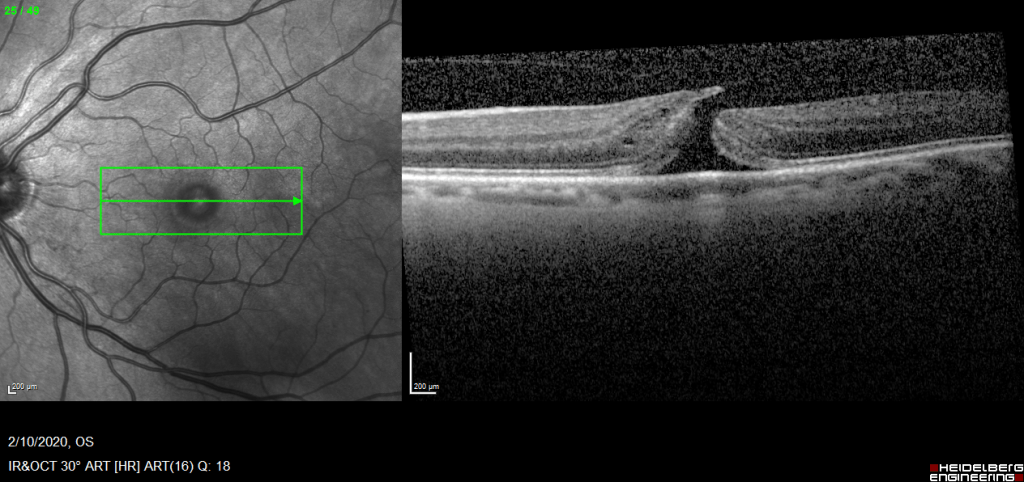

Case#2-PVH

Bilateral Macular holes. When to operate?